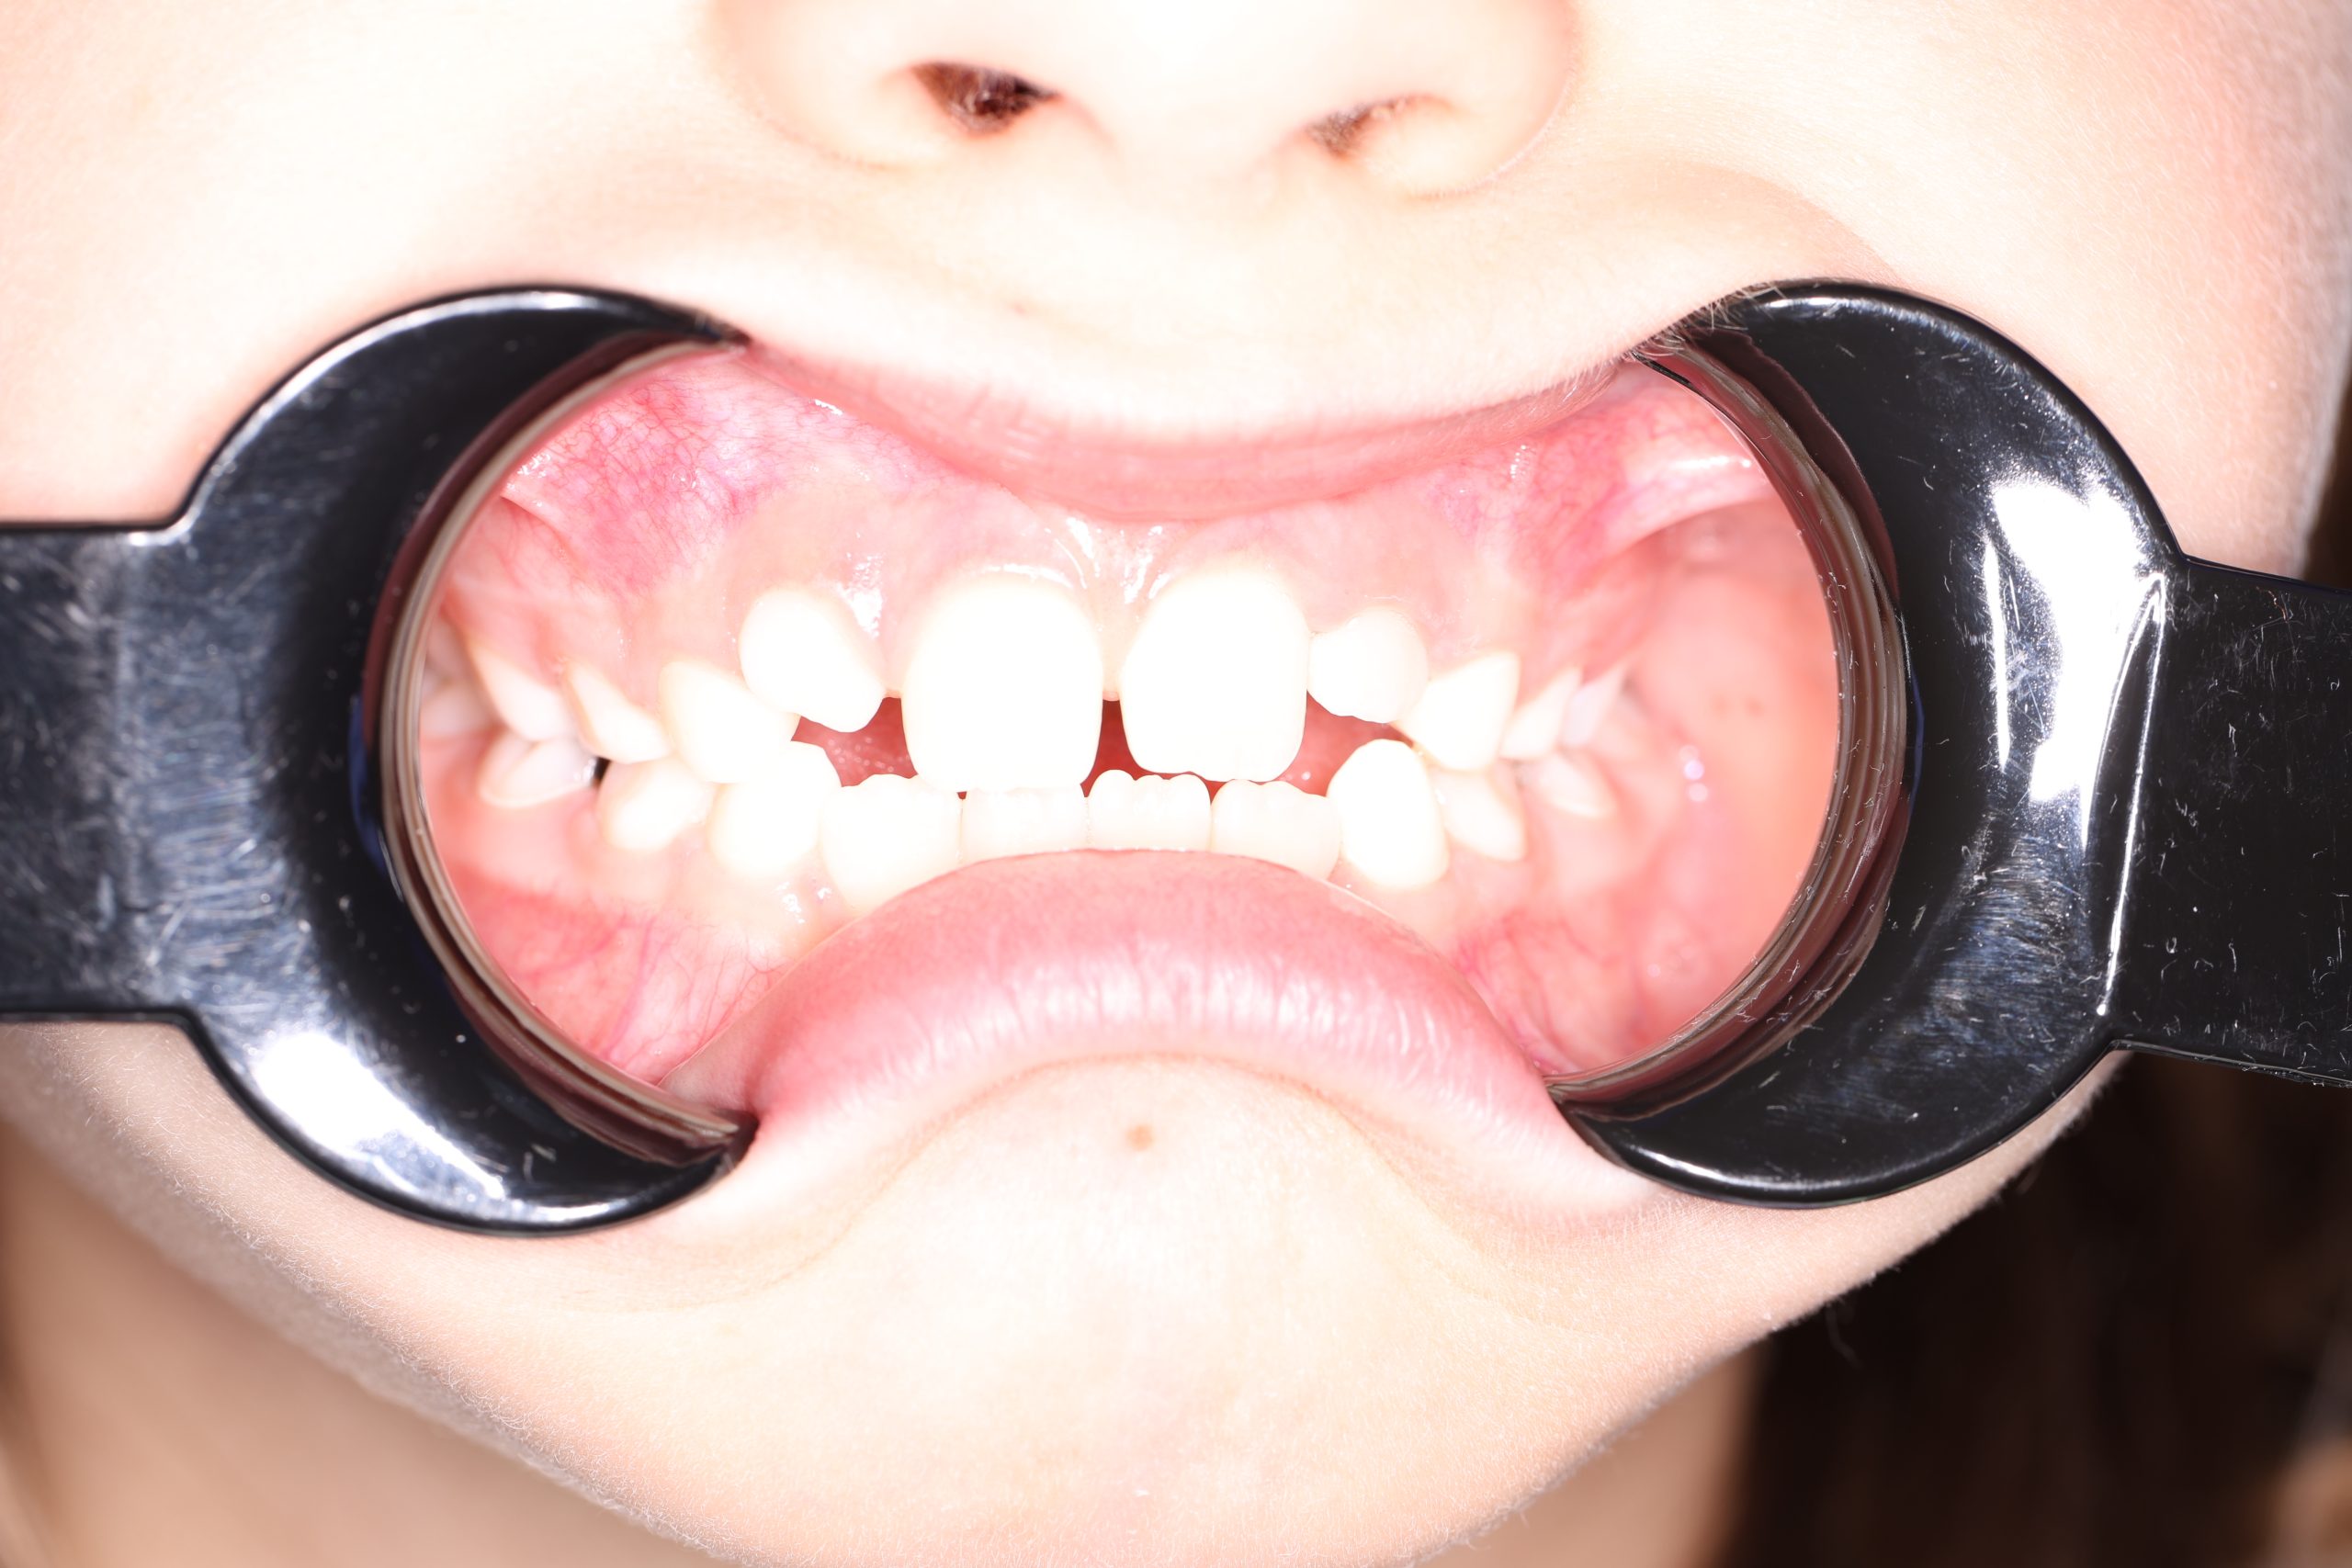

- There’s a structural defect in the enamel (due to developmental issues)

Tooth-Colored Composite Crowns

Perfect for front baby teeth. These crowns are designed to mimic the appearance of a real tooth as good as possible.

Zirconia Crowns

Aesthetic, white-colored crowns that are both beautiful and durable. Zirconia is usually installed on front teeth but can be used for molars as well.